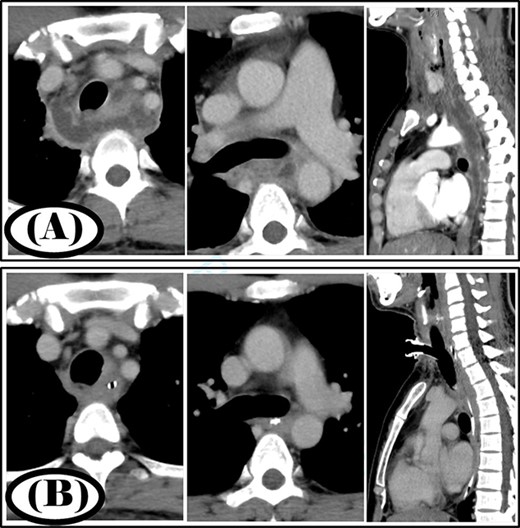

A 68-year-old woman was diagnosed with a posterior pharyngeal abscess triggered by a fever and sore throat. Cervicothoracic CT showed that the infection had spread to the mediastinum (Fig. 3A), and the patient was diagnosed with type IIB DNM. Cervical drainage and mediastinal drainage were performed simultaneously. Mediastinal drainage using only the cervical approach was sufficient. Streptococcus sanguinis was detected in the mediastinal abscess cavity. Continuous irrigation with saline (2 l/day) was initiated immediately post-surgery. The duration of irrigation, drainage and hospital stay were 10, 13 and 22 days, respectively. Four weeks post-surgery, cervicothoracic CT showed no abscess cavity and an improvement in infection was noted (Fig. 3B).

Case 3: pre- and post-treatment cervicothoracic CT; (A) pre-operative cervicothoracic CT and (B) cervicothoracic CT 4 weeks after treatment.